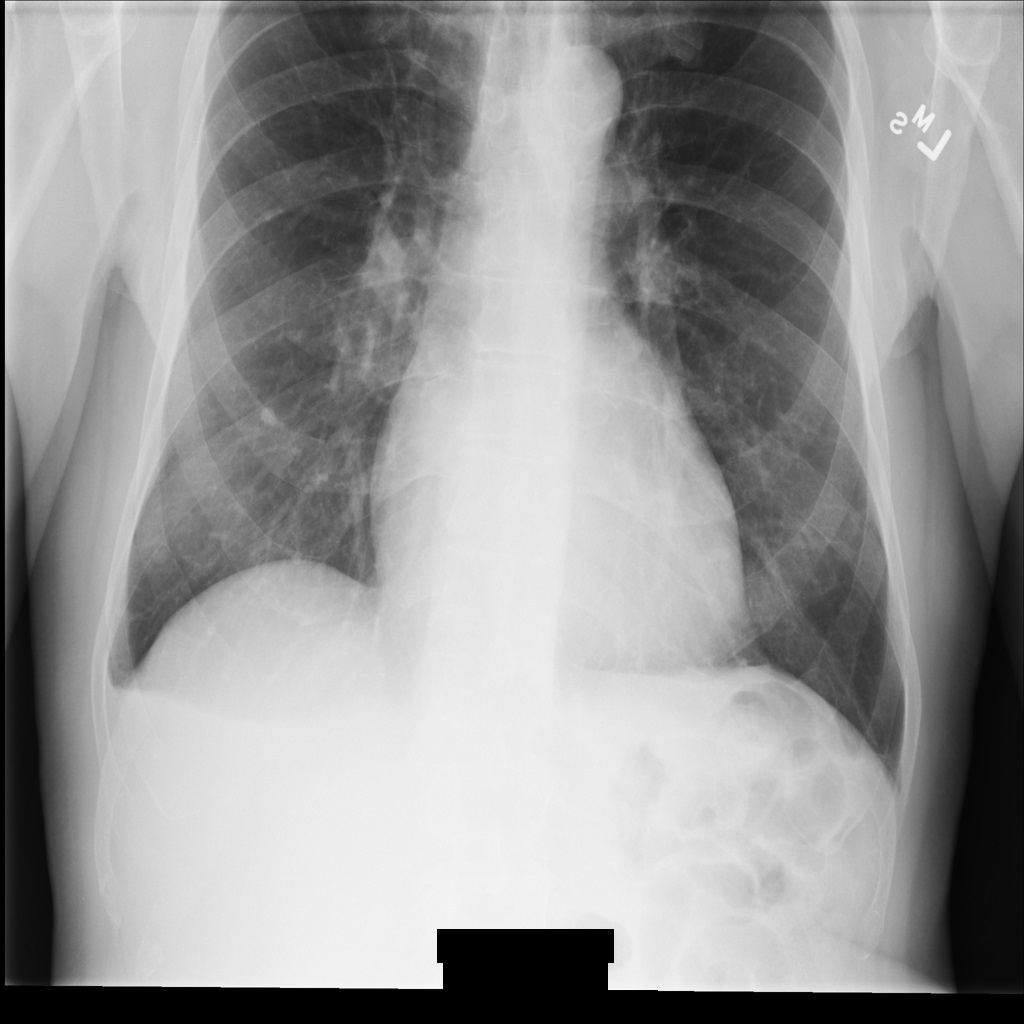

Imagem de exemplo

Alguns exemplos nesta página contêm uma saída da imagem desidentificada. Cada exemplo usa a seguinte imagem original como entrada. Pode comparar a imagem de saída de cada operação de desidentificação com esta imagem original para ver os efeitos da operação: